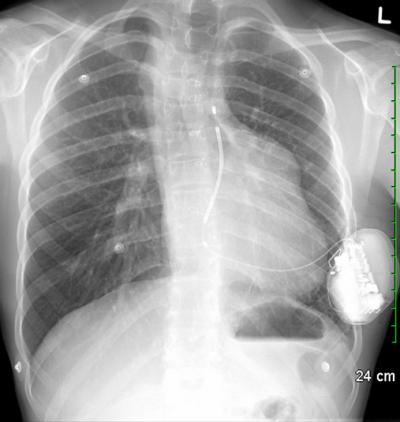

What makes the new device special is that it is entirely subcutaneous. No part of it actually touches the heart. Instead, an electrode is implanted just under the skin near the heart.

The defibrillator is connected to the electrode, and monitors the heartbeat at all times. If needed, it delivers a shock to the heart muscle to restore its normal rhythm.